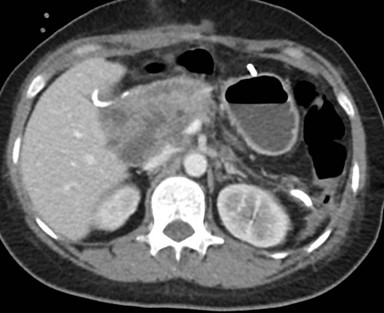

Caso 3

Mujer de 36 años que ingresa a Hospital Sanatorio Franchin el 11 de octubre de 2023 de forma programada para realización de duodeno pancreatectomía cefálica por tumor de cabeza de páncreas en estudio. Refiere hallazgo de lesión en forma incidental durante estudio de control hace dos meses por presentar antecedentes familiares (neoplasia endocrina múltiple). Se interna para manejo quirúrgico. Estudios de tomografía revelan formación nodular localizada en cabeza y cuerpo pancreático de paredes gruesas que mide 24 x 28 mm, que en resonancia se muestra hiperintensa en T2 y realce periférico luego de la administración de contraste endovenoso. Presenta restricción en la difusión con caída de la señal ADC, por lo que se vincula con una lesión de alta celularidad.

Se le practica una duodeno pancreatectomía cefálica y triple anastomosis (hepato yeyuno, gastroentero y wirsung enteroanastomosis) el 12 de octubre de 2023 y pasa a internación UTI, el 14 de octubre se complica con fiebre, dolor abdominal y fístula pancreática con dosaje de amilasa de drenaje >6000, por lo que se le realiza tomografía que muestra abundante líquido libre en cavidad. Por tal motivo se le realiza una exploración quirúrgica por laparotomía, encontrándose abundante líquido + pancreatitis en la anastomosis yeyuno pancreática. Se realiza lavado de cavidad + 3 drenajes abocados a zona pancreática + yeyunostomia.

Paciente que se intuba y pasa a UTI, posteriormente extubación exitosa. El 22 de octubre se complica con colección abdominal, por lo cual requiere de drenaje percutáneo guiado por TC.

Tomografía de abdomen y pelvis con cte ev: del 13/10/2023.

Complicaciones posquirúrgicas

Tomografía de abdomen con cte ev: del 20/10/2023.

Tomografía de abdomen con cte ev: del 26/10/2023.

Estudio histopatológico reveló neoplásica de estirpe neuroendocrina bien delimitada.